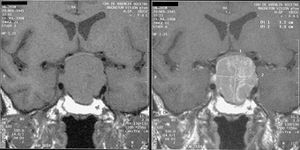

Magnetic resonance image of a pituitary macroadenoma that caused acromegaly with compression of the optic chiasm.